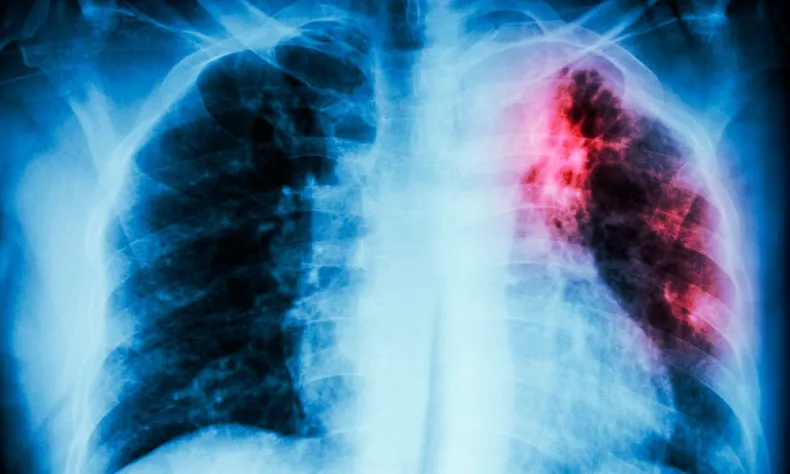

El Programa de Detección Temprana de Cáncer de Pulmón incorpora un circuito especializado que facilita el acceso a estudios de baja dosis para detectar lesiones pulmonares en etapas iniciales.

El cáncer de pulmón es una de las principales causas de mortalidad oncológica a nivel mundial y, en la mayoría de los casos, no presenta síntomas en sus etapas iniciales. Por este motivo, detectarlo a tiempo incrementa de manera significativa las posibilidades de tratamiento y supervivencia.

En este marco, el programa incorpora la realización de tomografías de tórax de baja dosis, un estudio rápido, gratuito y de mínima radiación, recomendado internacionalmente para la detección precoz.